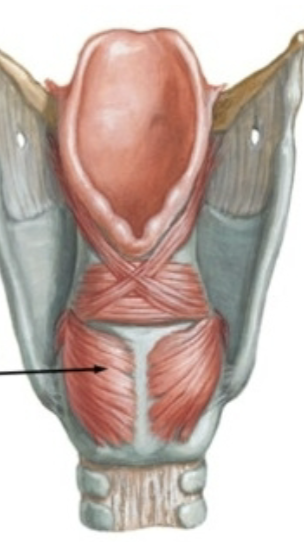

What is this muscle?

Posterior cricoarytenoid (PCA) (rocks arytenoid out, abduct VF)